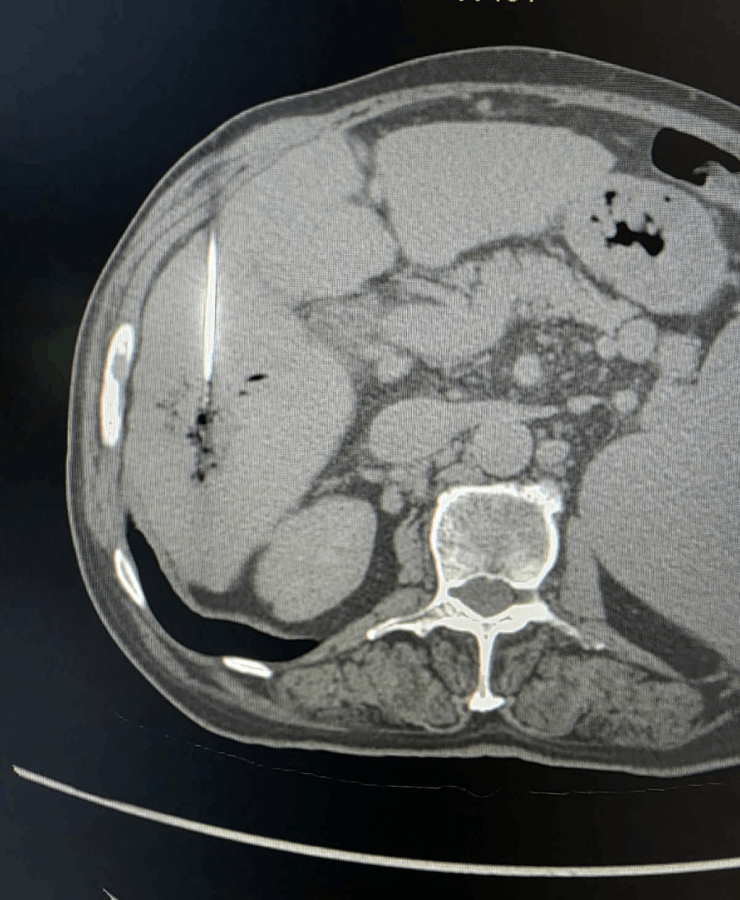

Liver Cancer Treatment

Many liver cancer patients are not suitable for surgery because of tumour location, multiple lesions, underlying liver disease or general health. In such cases, interventional radiological procedures can offer effective, targeted options:

Microwave ablation of liver cancers

Liver tumor

Before treatment liver cancer

After treatment of liver cancer